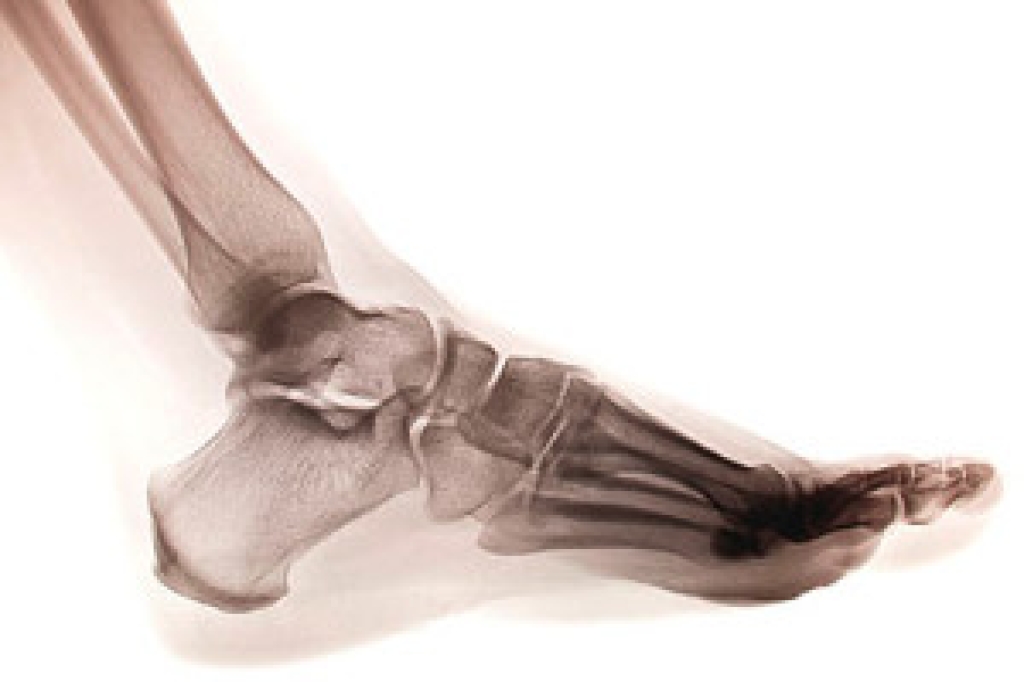

There are several bones in each foot, and a stress fracture occurs when there is a hairline break in one of the small bones. It often happens as a result of repetitive stress the feet endure from running or from frequently participating in jumping activities. The fractures are typically very small, despite how painful they can be. Many people choose to ignore the nagging pain in their foot, and it often becomes worse if it is not promptly treated. It may be a common injury among runners who increase their speed and frequency of running too soon, and this could gradually cause a stress fracture. This can be a result of a lack of strength and endurance from the muscles that cannot cope with added support that is needed when that activity increases. Additional reasons why stress fractures may occur include having an abnormal foot structure, wearing shoes that do not fit correctly, or having previous stress fractures. If you think you have endured this type of fracture, please speak with a podiatrist as quickly as possible who can properly treat this condition.

Stress fractures occur in the foot and ankle when muscles in these areas weaken from too much or too little use. The feet and ankles then lose support when walking or running from the impact of the ground. Since there is no protection, the bones receive the full impact of each step. Stress on the feet can cause cracks to form in the bones, thus creating stress fractures.